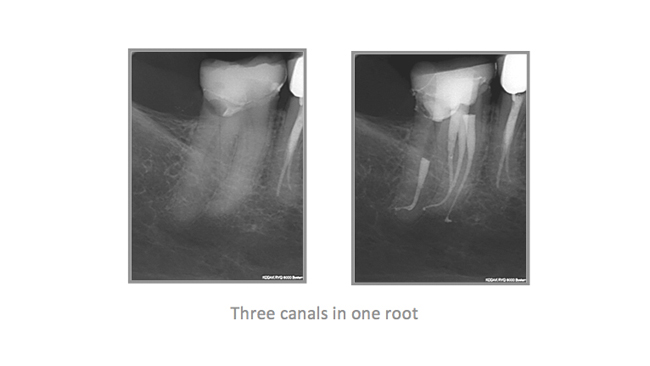

• A few Teeth Treated by Dr. Katsarsky